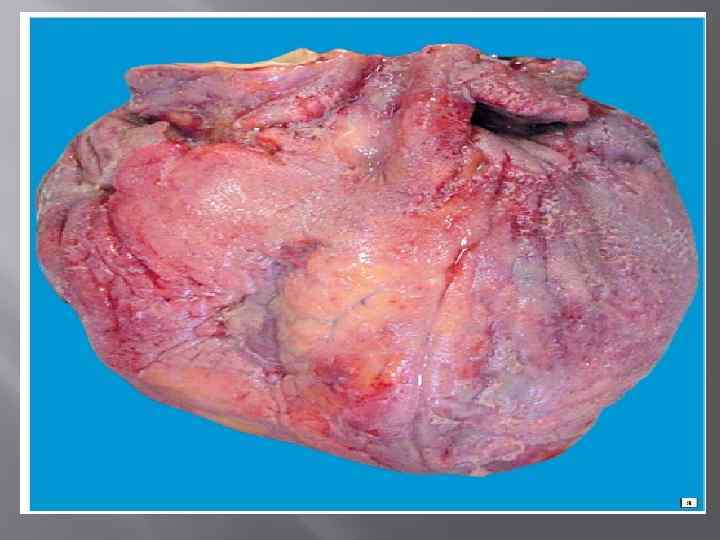

Фибринозды қабыну фибриногенге бай экссудаттьщ жиналуымен сипатталады Фибриноген белогі жергілікті тромбопластин факторларының әсерінен фибринге айналады. Фибрин жіпшелері сірі қабьщтардьщ үсіінде түк сияқтаньш, қабыр шақтанып, үйып қалады. Мүндай жүректі "түкті" жүрек дейді. Фибринозды қабынудың крупоздық және дифтериттік түрлерін ажыратады. Фибринозды қабынудың былайша болінуі сол жерде некроздың тереңдігіне және эпителидің сипатына тәуелді. Қабы нудың дифтериттік түрінде пайда болған қабыршақты сүр қабат астындағы тіннін терең некрозына байланыст^і оған сіңіп ажырамастай болып бірігіп қалады. Осы қабыршық қабатпен айнала сындағы тін арасында бөлуші шекара (демаркация сызығы) түзіледі. Осы жерде жиналған лейкоциттер ферменттерінің өсерінен фибринді қалың қабық еріп, бірте сыдырылып түсе бастай ды. Қабынудың бүл түрі көп қабатты эпителимен қапталған ағза ларға: жүтқыншаққа, бадамша бездерге, өңешке, дыбыс желбезегіне, қынапқа төн (37 сурет).

Крупоздық қабынукөбінесе сірі қабықтарда кездеседі. Пайда болған қабыршық қабат оңай алынады, себебі бүл үрдіс тін некро зы беткей жайғасқан кезде немесе цилиндрлік эпителимен жабыл ған ағзаларда ғана дамиды. Бүған фибринозды плеврит, перикар дит, өкпенің крупоздық қабынуы мысал бола алады (38 сурет). Фибринозды қабынудьің себептері көбінесе инфекцияларда байланысты. Күл (дифтерия), дизентерия тудыратын таяқшалар, пневмококтар, Френкель диплококктары т. б. қабынудың осы түрін қоздырады.